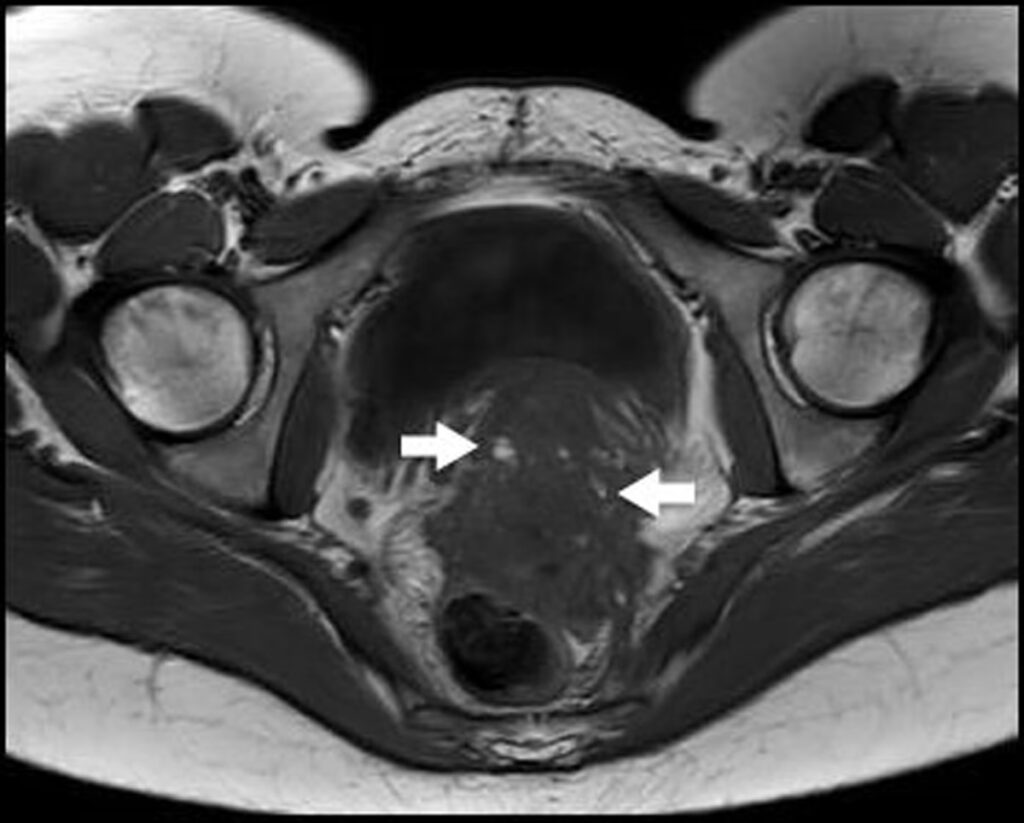

På en MRI-scanning fremstår DIE-læsioner typisk som mørke, fibrøse knuder eller fortykkelser på T2-vægtede billeder. De kan indeholde små, lyse pletter, som repræsenterer indkapslede blødninger. Almindelige placeringer for DIE, som MRI er særligt god til at visualisere, inkluderer:

- De uterosakrale ligamenter: Disse ligamenter, der støtter livmoderen, er den hyppigste placering for DIE. MRI kan vise fortykkelse, nodularitet og sammenvoksninger til omkringliggende strukturer.

Derudover kan MRI identificere sekundære tegn på endometriose, såsom "kissing ovaries", hvor adhærencer trækker begge æggestokke sammen bag livmoderen, hvilket er et tegn på fremskreden sygdom.